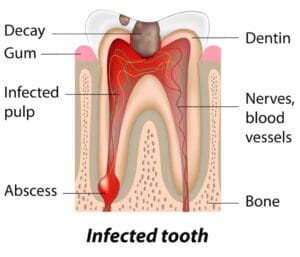

التسوس يضعف بنية السن من الداخل ويجعل طبقاتها أقل صلابة وأكثر عرضة للكسر والتشقق حتى مع ضغوط يومية عادية مثل الأكل أو المضغ. عندما يمتد التسوس إلى العاج أو يقترب من عصب السن، تصبح المينا كالغلاف الهش الذي يمكن أن ينكسر بسهولة، ما يؤدي إلى تشقق جزء من السن أو انهياره. علاج التسوس مبكرًا وحشو الأسنان المتضررة يحميها من الانقسام والتشقق، ويساعد في الحفاظ على قوة بنية السن ومنع المضاعفات المؤلمة المرتبطة بتشقق الأسنان.

تتحول أسباب تشقق الأسنان البسيطة، مثل قضم الأشياء الصلبة أو صرير الأسنان الليلي أو التعرض لصدمة خفيفة، إلى مشكلة خطيرة عندما يبدأ الشرخ في التعمق والوصول إلى طبقات السن الداخلية والعصب. عندها قد تظهر أعراض مزعجة مثل ألم حاد عند المضغ، أو حساسية قوية للمشروبات الباردة والساخنة، أو ألم متقطع يصعب تحديد مصدره. تجاهل هذه العلامات قد يؤدي إلى التهابات شديدة في العصب أو تكون خراج تحت السن، ما يهدد بفقدان السن بالكامل والحاجة إلى علاج عصب أو خلع. لذلك، إذا لاحظت أي تغيير في شكل السن، أو شعرت بألم مفاجئ بعد تناول شيء قاسٍ، أو ازدادت حساسية الأسنان دون سبب واضح، فهذا مؤشر على أن تشقق الأسنان لم يعد مشكلة بسيطة ويستدعي زيارة عاجلة لطبيب الأسنان لتشخيص الحالة مبكرًا ومنع تطورها إلى مضاعفات خطيرة.